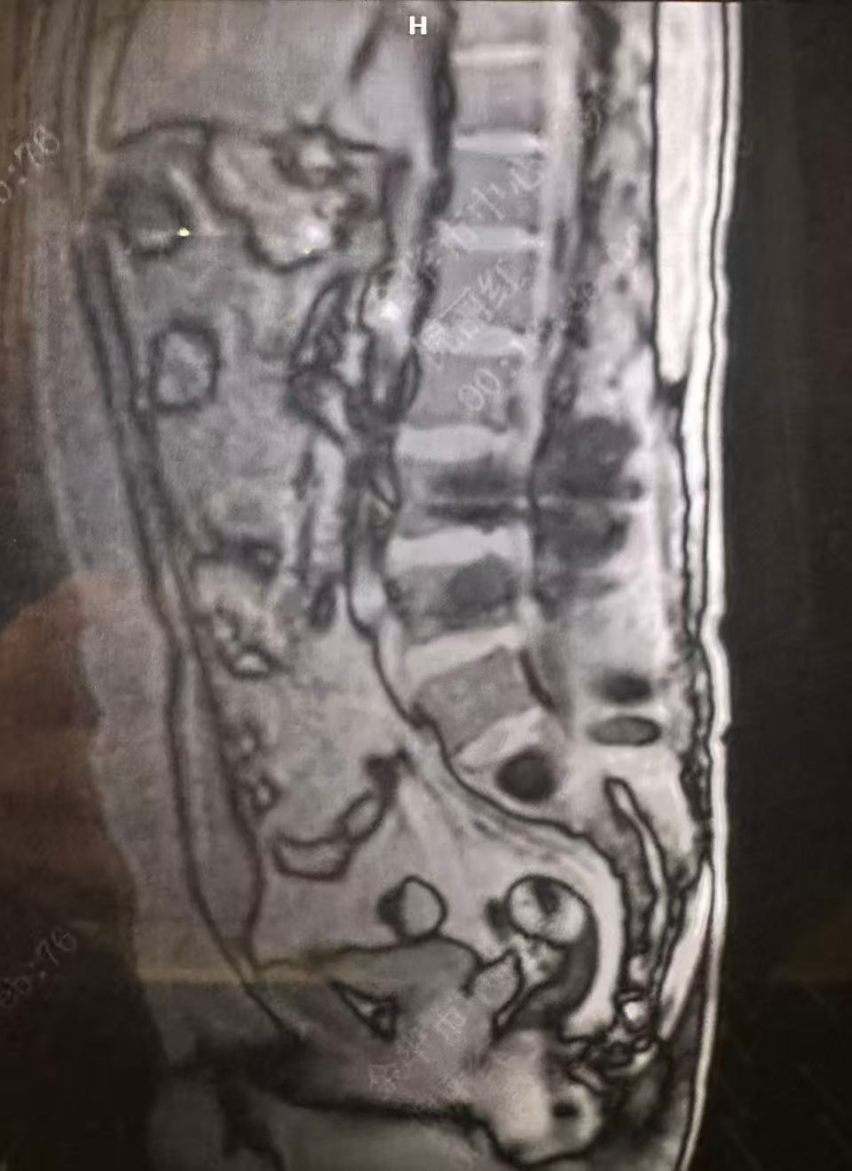

2025年4月12日患者入住本院,4月13日复查示:血常规白细胞4.22×109/L,血红蛋白114 g/L,血小板184×109/L;骨髓幼浆细胞占0.5%;MRD检测到0.03%单克隆性异常浆细胞。评估病情达部分缓解。MR检查示腰椎平扫1. 5:腰骶椎术后表现;所见胸腰骶椎弥漫性信号异常,骶2椎体异常强化影,符合多发性骨髓瘤表现(图1)。

图1. MR检查结果